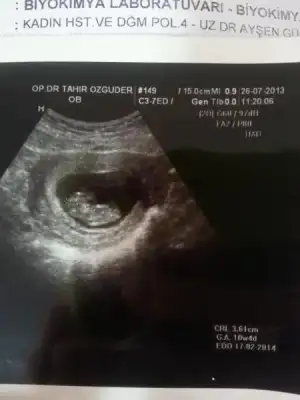

Eki Görüntüle 807467 ust kısımında kesenın dıbınde kanama alanı gozukuyor doktor hersey olabılır kan kuruyup yapısabılır dedı

Canım bak bende ekliyorum kanama alanını. Bizimki ilişki sonrası olmuştu. Doktor 2-3 gün güzelce dinlen geçer demişti ama kanamam tam 3 gün aralıklarla sürdü. Bi ara ped bile kullandımm. Korkma.

Bebişkomun şimdiki halini de ekliyorum rahatla :54::54:

Hayır canım alt tarata bi koyuluk var çizgi halinde. Kesenin etrafında vardı hep öyle çizgi çizgi. Geçti sonradan çok şükür. İnternette yazılanları okuyup okuyup telaşlanmıştım sen yapma. Yat dinlen.